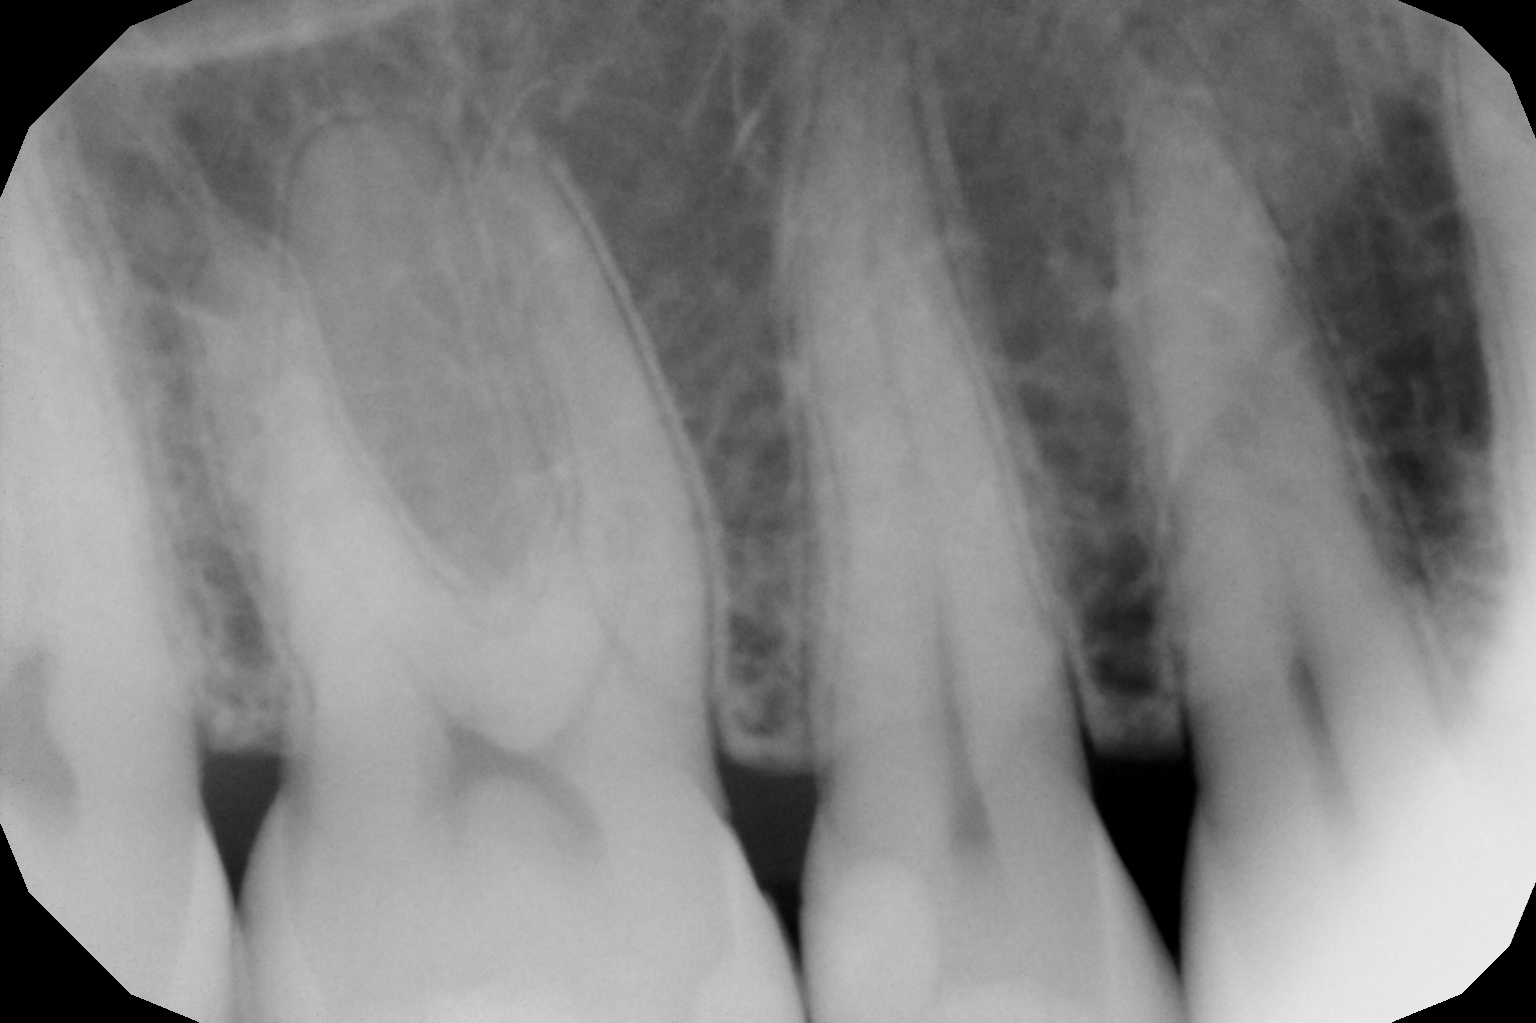

Si presenta alla nostra attenzione per dolore in zona premolare e molare del primo quadrante. Dopo un’analisi clinica e strumentale con radiografie e test diagnostici, si evidenzia la necessità di sostituire le precedenti otturazioni in composito, al fine di consegnare un migliore punto di contatto (fenomeno dell’impact food).

foto 1 Fotografia iniziale

foto 12 Aspetto radiografico